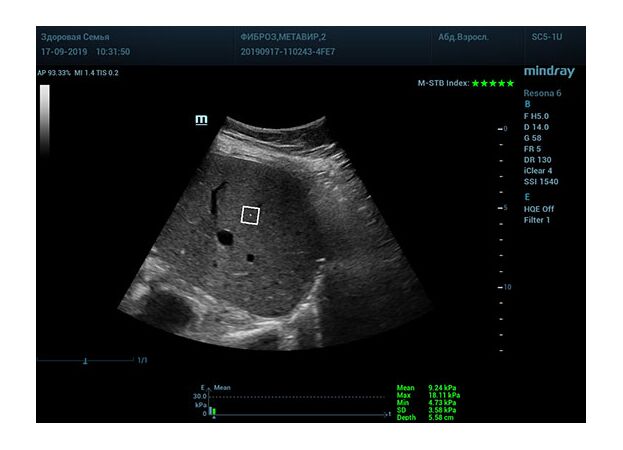

Определение плотности печени. Не ошибся ли оператор при измерении эластических свойств печени? Для оценки критериев качества предусмотрен индекс MBT, который покажет насколько «твердой» была рука оператора и двигалась ли печень. При MBT 5* рука тверда и показатели достоверны. Для оценки качества результатов используется IQR индекс, отображающий колебания показателей в точке измерения при расчете медианы. Показатели при IQR <30% считаются приемлемыми. Техника сканирования через межреберные промежутки требует размещение окна интереса на несколько сантиметром ниже капсулы, для исключения эффекта реверберации. Установка ROI на паренхиму без захвата сосудов, для исключения погрешностей измерения.

Стадия фиброза определяется по системе METAVIR Staging, построенной на данных биопсии и сопоставлении с данными эластографии. Своевременная диагностика фиброза, и начало его лечения, залог благоприятного исхода заболевания.

• METAVIRF2 – Портальный фиброз с вовлечением нескольких перегородок